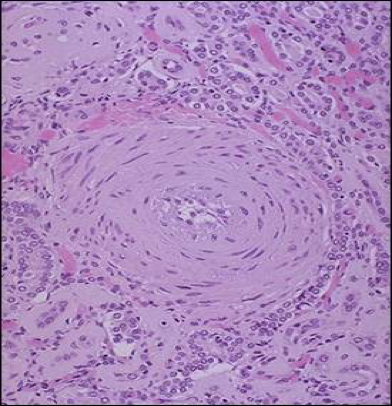

1. 增生性小动脉硬化,主要发生在肾小叶间动脉及弓形动脉等处,主要表现为内膜显著增厚,内弹力膜分裂,SMC增生肥大,胶原等基质增多,使血管壁呈同心层状增厚,如洋葱皮样。病变主要累及肾和脑血管,常致肾、脑发生缺血性坏死和出血等,严重损害肾、脑功能。